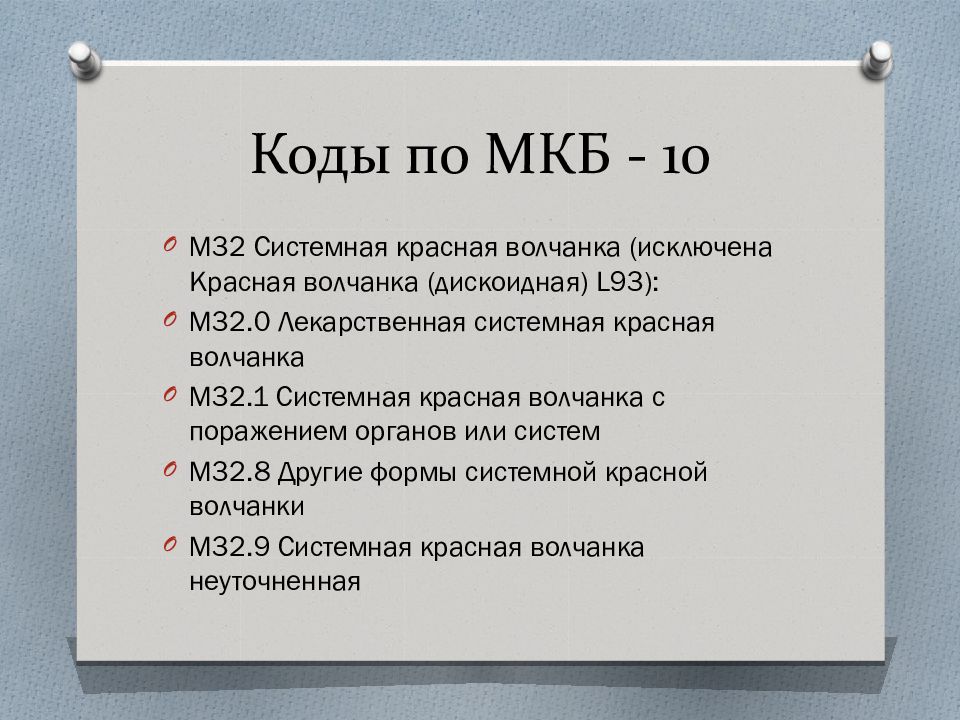

Код мкб 10 атерома головы

Код мкб 10 атерома головы 109 фото